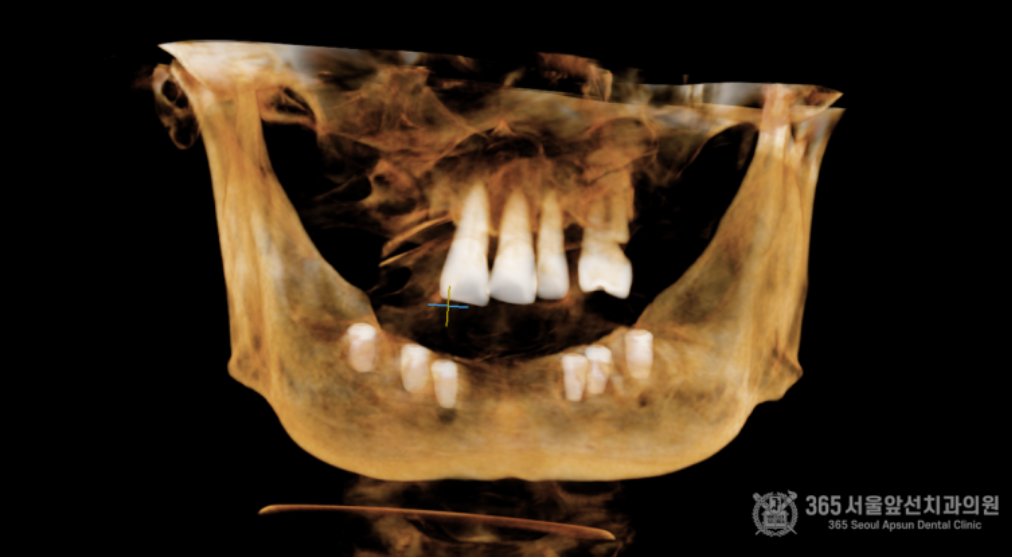

통증이 두려워서 무절개로 수술을 하고 싶어요. 무절개 임플란트 수술을 문의 주셨던 환자분입니다. 윗턱에는 불편하지만 사용하시던 틀니가 있기에, 일단은 아랫턱만 임플란트 수술을 원하셨습니다. 촬영일시 : 2024.05.14. 초진 내원 당시 구강내 엑스레이 사진입니다. 보시다시피 아랫턱은 완전 무치악으로 치아가 전혀없습니다. 무절개 방식을 사용하여군더더기 손 동작 없이 정확하고 빠르게 15분만에 수술을 마무리 해드렸습니다ㅎㅎ 충분한 숙련도를 갖춘 의료진이라면 불필요한 디지털 가이드 방식의 수술이나 복잡하고 번거로운 도구없이 감각만으로 빠르고 정확한 수술이 가능합니다. 지금까지 만 개 이상의 임플란트를 식립해오면서 얻게 된 수술 경험으로 불필요한 과정없이 필요한 술식만으로 임플란트 수술을 진행하고 있습니다. 촬영일시 : 2024.05.14. 수술 직후 3차원 CT입니다. 정확한 위치에 올바른 각도와 간격으로 임플란트들이 가지런히 식립되어있습니다. 촬영일시 : 2024.08.22. 4개월 후 완성 후 사진입니다. 지금까지 365일 늘 가까운 서울대학교 치과병원을 지향하는, 365서울앞선치과 강동우 대표원장이었습니다! 앞으로도 도움이 되는 증례로 찾아뵙겠습니다. 감사합니다. [ 치료기간: 2024년 5월14일 ~2025년 8월 22일 )] |